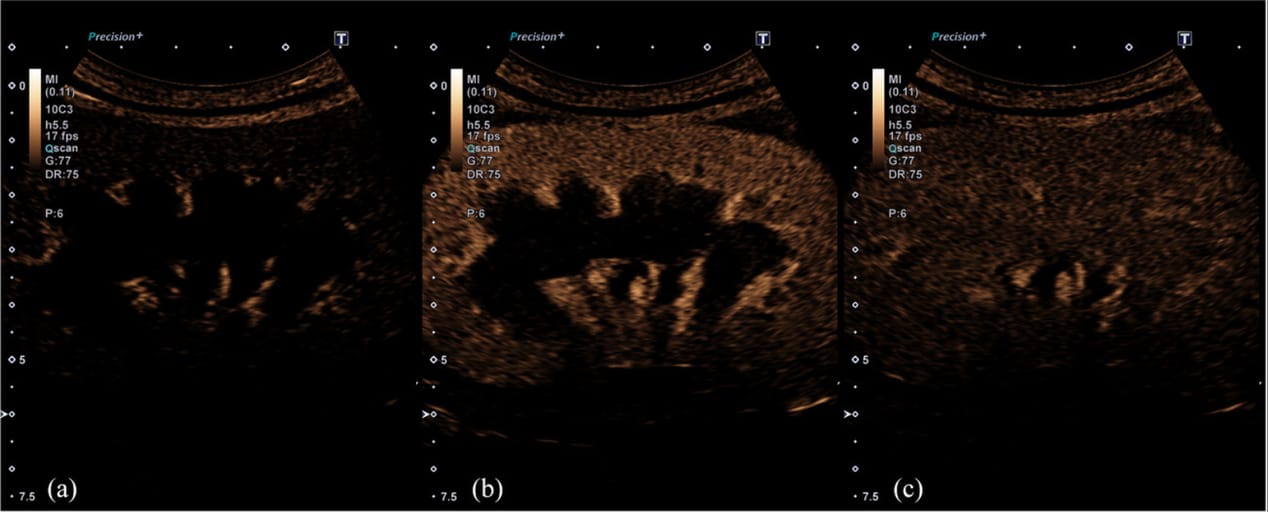

Contrast-enhanced ultrasonography images showing enhancement of the interlobar arteries (a), the renal cortex (b) and the renal medulla (c) of a dog with acute kidney injury

CEUS provided valuable prognostic insights, with specific perfusion patterns correlating to survival and renal recovery rates. Dogs with more homogeneous contrast uptake and prolonged perfusion times had better outcomes, while those with severely reduced perfusion showed poorer prognoses. CEUS outperformed some traditional biomarkers in predicting clinical trajectories.